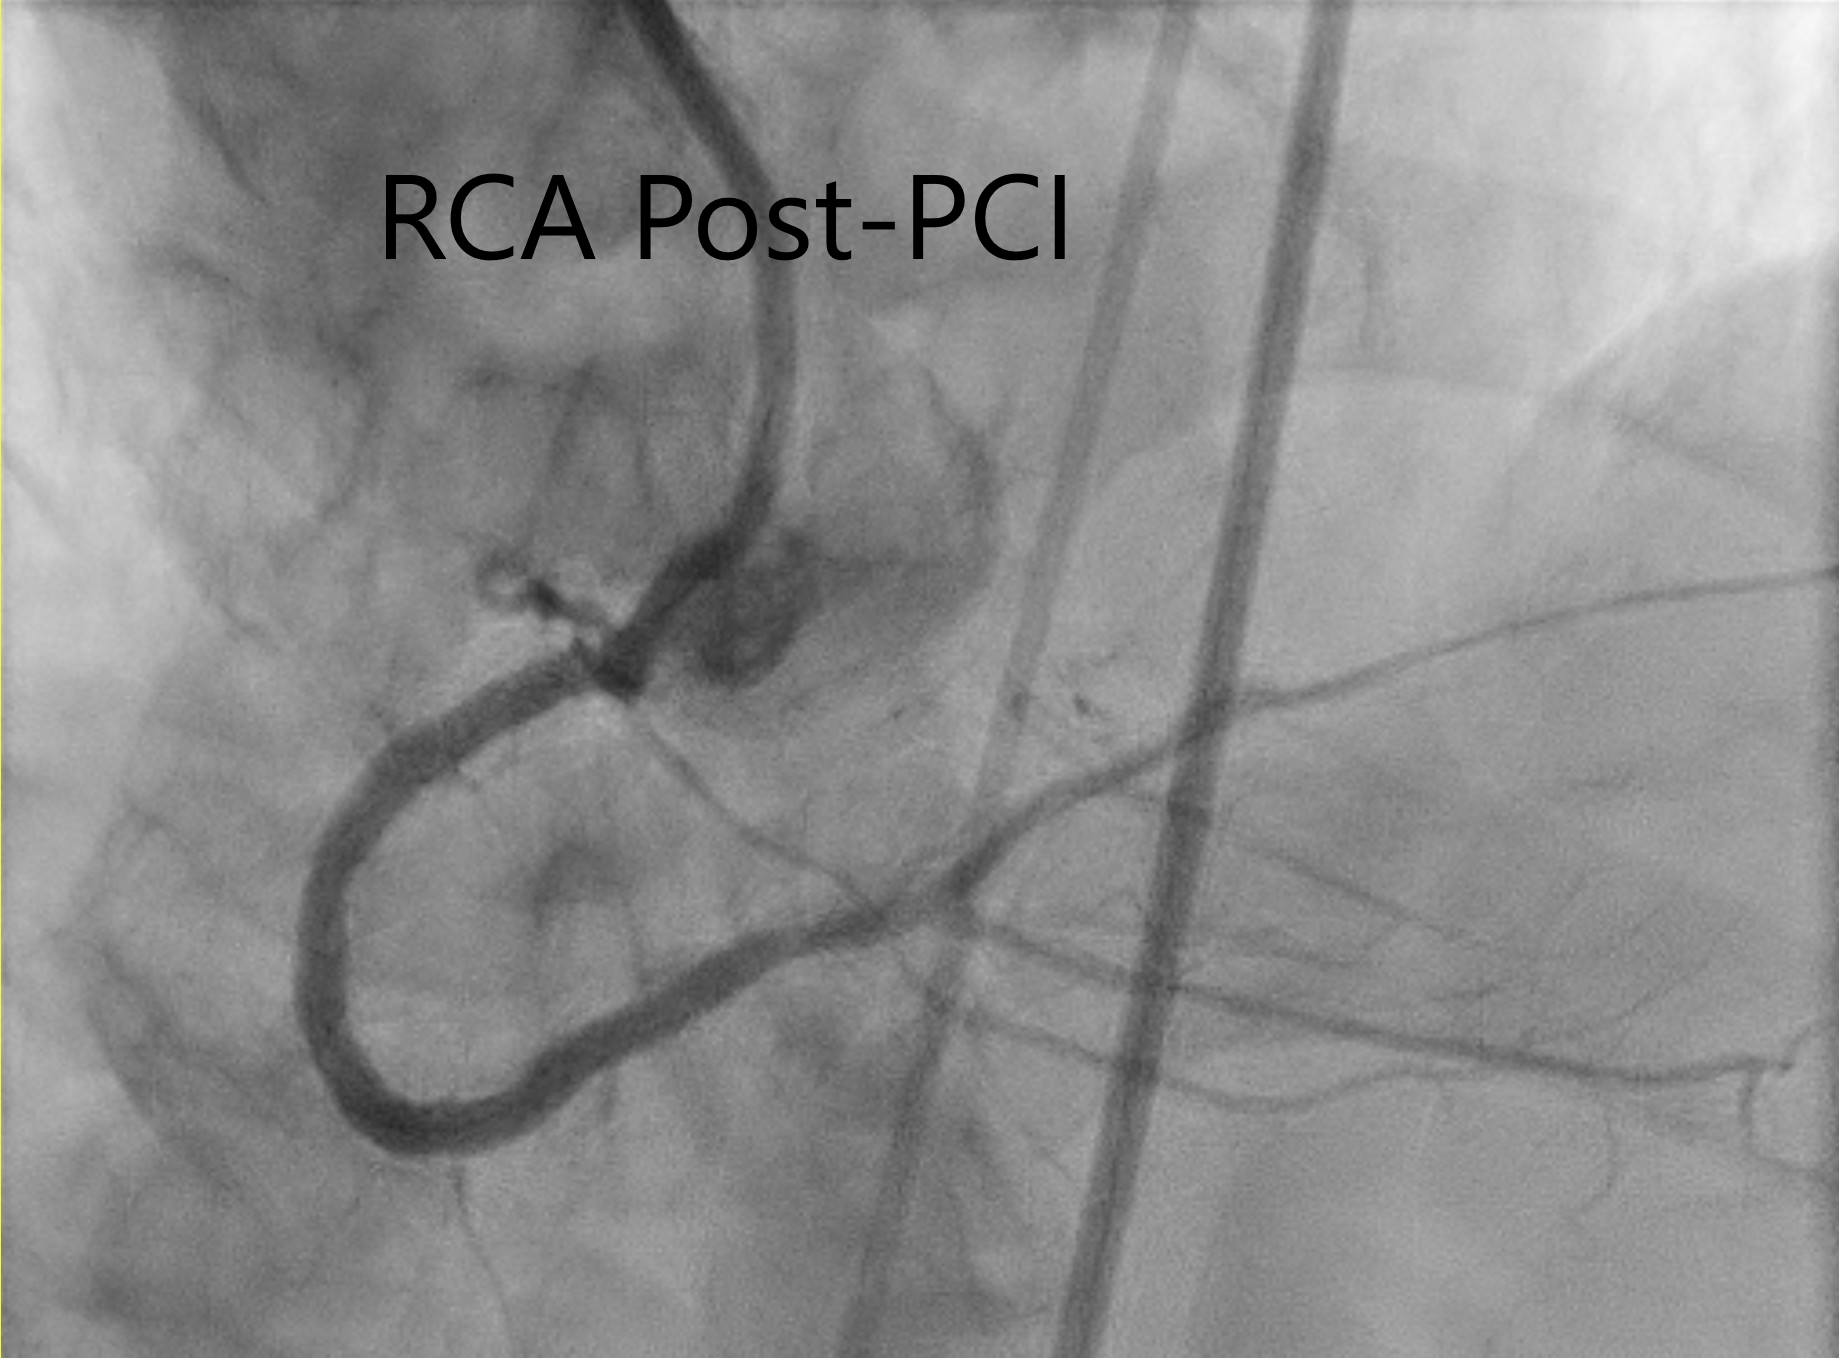

Bifemoral approach. 7F and 5F sheaths in the right and left respectively. Heparin 7000 units. 7F Cordis AL1 GC and 5F APT JL4 DC were inserted with 0.035 J-tip Teflon wire (B Braun). Starting BP 158/72 mmHg. RCA stenoses and CTO were successfully crossed Gaia 3rd wire (Asahi). Distal RCA stented with DES 2.75x34 and ostial-mid RCA stented using DES 3x46mm (iVascular). Immediately after this, 2nd stent was placed. His sBP dropped from 134 to 70 mmHg over 2 minutes. A presumed diagnosis of vasovagal response was made. IV Atropine 0.5 mg bolus, IV Adrenaline 0.5 mg bolus, IV normal saline bolus were given. Immediate echo showed no pericardial effusion. Before sheath removal, the patient developed his BP dropped to 70 mmHg. IV infusion of Noradrenaline given. Bilateral iliac and femoral angiogram showed no evidence of bleeding from the puncture sites. The patient developed distended abdomen. Urgent CT abdominal scan showed a large right sided mesenteric mass with dilated tortuous vessels in keeping with a pseudoaneurysm. A diagnosis of ¡°intraperitoneal arteriovenous malformation bleeding with feeding arteries from SMA¡± was made.The patient underwent urgent embolization of the bleeding sites using using 7 pushable helical coils: 3 of 4 x 40 mm coils and 4 Vortx Diamond pushable coils (4 x 3.77 mm) (Boston Scientific). Repeat DSA and angiogram 1 minute and 5 minutes later showed no more bleeding.